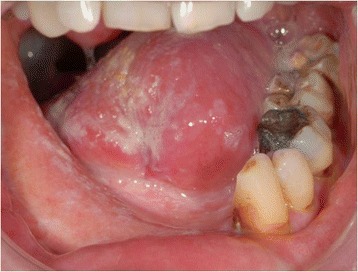

Figure 1.

The computed tomography illustrates a tumor on the right floor of the mouth (arrows). Radiographically there is the suspicion of an erosion of the cortical bone of the lower jaw.

A written consent for this case report has been obtained by the patient. The patient is a 52-year-old male Caucasian, residing in the south of Germany. There was no specific family history of malignancy. As far as risk factors are concerned the patient has a smoking history adding up to 45 pack years and still smokes about 10 to 15 cigarettes per day. There was no alcohol consumption reported. He was referred by his dentist to our Department in February 2013 with a suspected OSCC of the floor of the mouth. The conducted head and neck computed tomography (CT) strengthened the clinical suspicion of an OSCC of the right floor of the mouth; a tumor that was also infiltrating the right mandible was demonstrated, along with enlarged lymph nodes at both sides of the neck [Figure 1]. As a part of the staging and planning procedures a laryngoscopy and a pharyngoscopy were performed, as well as biopsies and marking of the boundaries of the tumor with a safety distance. Upon histopathological confirmation of the suspected OSCC diagnosis, the case was discussed during a meeting with our Multidisciplinary Team (MDT), when a primary surgical treatment was recommended. In March 2013 a tumor resection combined with a right mandibulectomy, a neck dissection at level I-V at the right side and level I-III at the left side and a simultaneous reconstruction with a vascular fibular transplant were performed. The histopathological examination of the resected specimen showed a moderately differentiated squamous cell carcinoma with perineural infiltration and one nodal metastasis (pT3 pN1 (1/46) L0 V2 Pn1 G3, local R0) [Figure 2a]. The histology of a macroscopically visible nodule in the neck dissection specimen showed a hemangiosis carcinomatosa (V2) [Figure 2b]. During his stay a heparin-induced thrombocytopenia (HIT) was diagnosed. After a consultation with our Department of Transfusion Medicine the thromboprophylaxis regime was switched from Enoxaparin 20 mg s.c. 1-0-0 to Danaparoid 750 IE s.c. 1-0-1. The postoperative MDT recommended radiation therapy. A locoregional radiation was performed from April 2013 to June 2013 (intensity modulated radiation therapy (IMRT) with a daily fraction of 2,1/1,8 GyHD 65,1/55,8 Gy). After radiation the patient joined our six-weekly tumor-follow-up at our department. Seven months later the decision for the removal of the osteosynthesis plate (Stryker GmbH & Co.KG, Duisburg, Germany, 2.7 mm) of the lower jaw was made and a panoramic radiograph as well as a CT were performed [Figure 3]. It showed no signs for a relapse of the OSCC but pseudarthrosis at two sides of the reconstructed mandible. The pseudarthrosis was treated with a bone graft from the iliac crest. During the surgical procedure several soft tissue biopsies from the right floor of the mouth were taken. No relapse was found within the obtained material. Five months later the decision for the removal of the miniplates (Stryker GmbH & Co.KG, Duisburg, Germany, 2.0 mm), used for the fixation of the iliac crest bone graft, was made. In March 2014 the patient showed up for surgery [Figure 4]. During the clinical examination the patient reported that he has detected a growing mass at his left upper arm about four weeks ago. Clinically the tumor was miming an abscess with redness, heat, swelling and moderate pain. The upper arm was x-rayed and a swelling of the soft-tissue in projection to the lower margin of the deltoid muscle was found [Figure 5]. Sonographically a differentiation between abscess and soft-tissue tumor could not be done [Figure 6]. Therefore MR-Imaging was performed. The MRI described an inhomogeneous tumor at the proximal upper arm with circular extent around the humerus up to the axilla [Figure 7]. Local arrosions of the corticalis suggested malignancy; however, a differentiation between a soft-tissue tumor and a metastatic tumor spread was not possible. Therefore a biopsy was taken and the histological examination revealed a widely necrotic moderately differentiated keratinizing squamous cell carcinoma (G2) [Figure 8]. The case was discussed in an Interdisciplinary MDT. Due to the tumor localization - wrapping the humerus and in close proximity to the brachial plexus and the vascular bundle - the decision to manage it with radiation was made. The patient decided to start radiation therapy at his local hospital. When he showed up for therapy a picture was taken. Noticeable was the rapid progress of the metastasis after the biopsy was taken with a clear infiltration of the skin. Experimental and clinical studies have shown rapid local growth after traumatic interventions, possibly explaining the progress [Figure 9] [4-9].